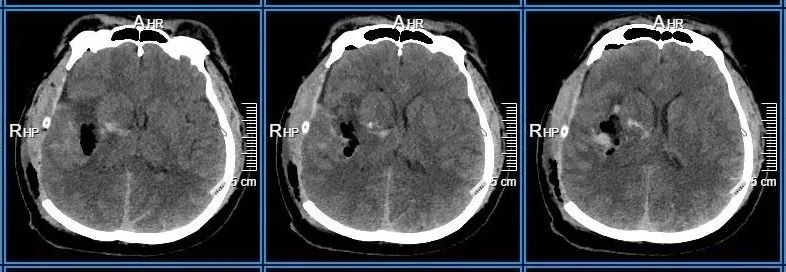

术前检查

患者到院时已处于昏迷状态,左侧肢体瘫痪,凭借医护团队丰富的经验,初步判断为急性脑血管意外。医护人员迅速开通绿色通道,完善检查,结果提示「右侧颞顶枕脑出血,脑疝」,排除脑血管畸形、脑动脉瘤破裂等,确诊为「高血压脑出血」。